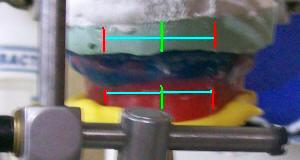

- Para el montaje en el articulador semi-ajustable, las guía

condileas deben tener una inclinación de 30º y el ángulo de Bennet

debe ser igual a 0º

Montaje del

modelo superior con arco facial anatómico |

|

|

|

Referencias

del rodete superior pasadas al modelo de trabajo |

|

|

|

|

Observe las marcas de los

rodetes en la silicona |

Montaje en

articulador con demasiado material |